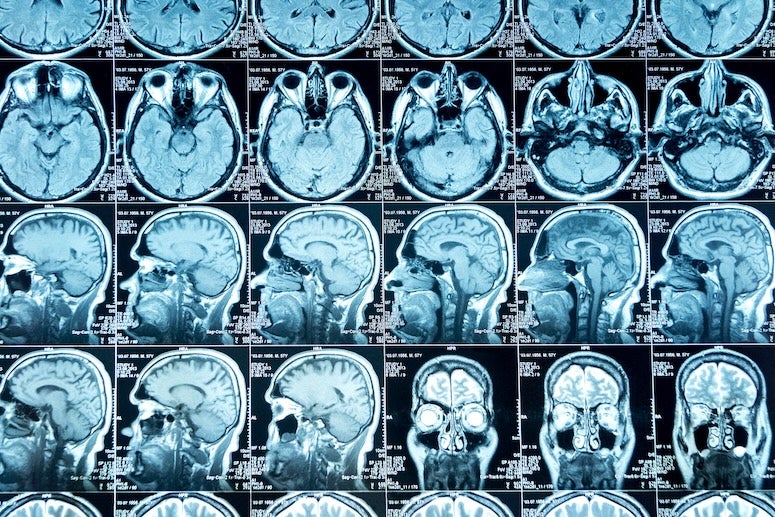

Deep sleep is essential for clearing waste products from the brain through the flow of cerebrospinal fluid. These nightly “cleaning cycles” help remove toxic proteins, such as amyloids, that accumulate during the day and are linked to Alzheimer’s disease and other dementias.

“Our goal is to measure and improve the brain’s ability to clear waste during deep sleep,” Aazhang said. “We are building a system that not only tracks the brain’s clearing process but can also stimulate it, improving natural mechanisms that protect against neurodegeneration.”